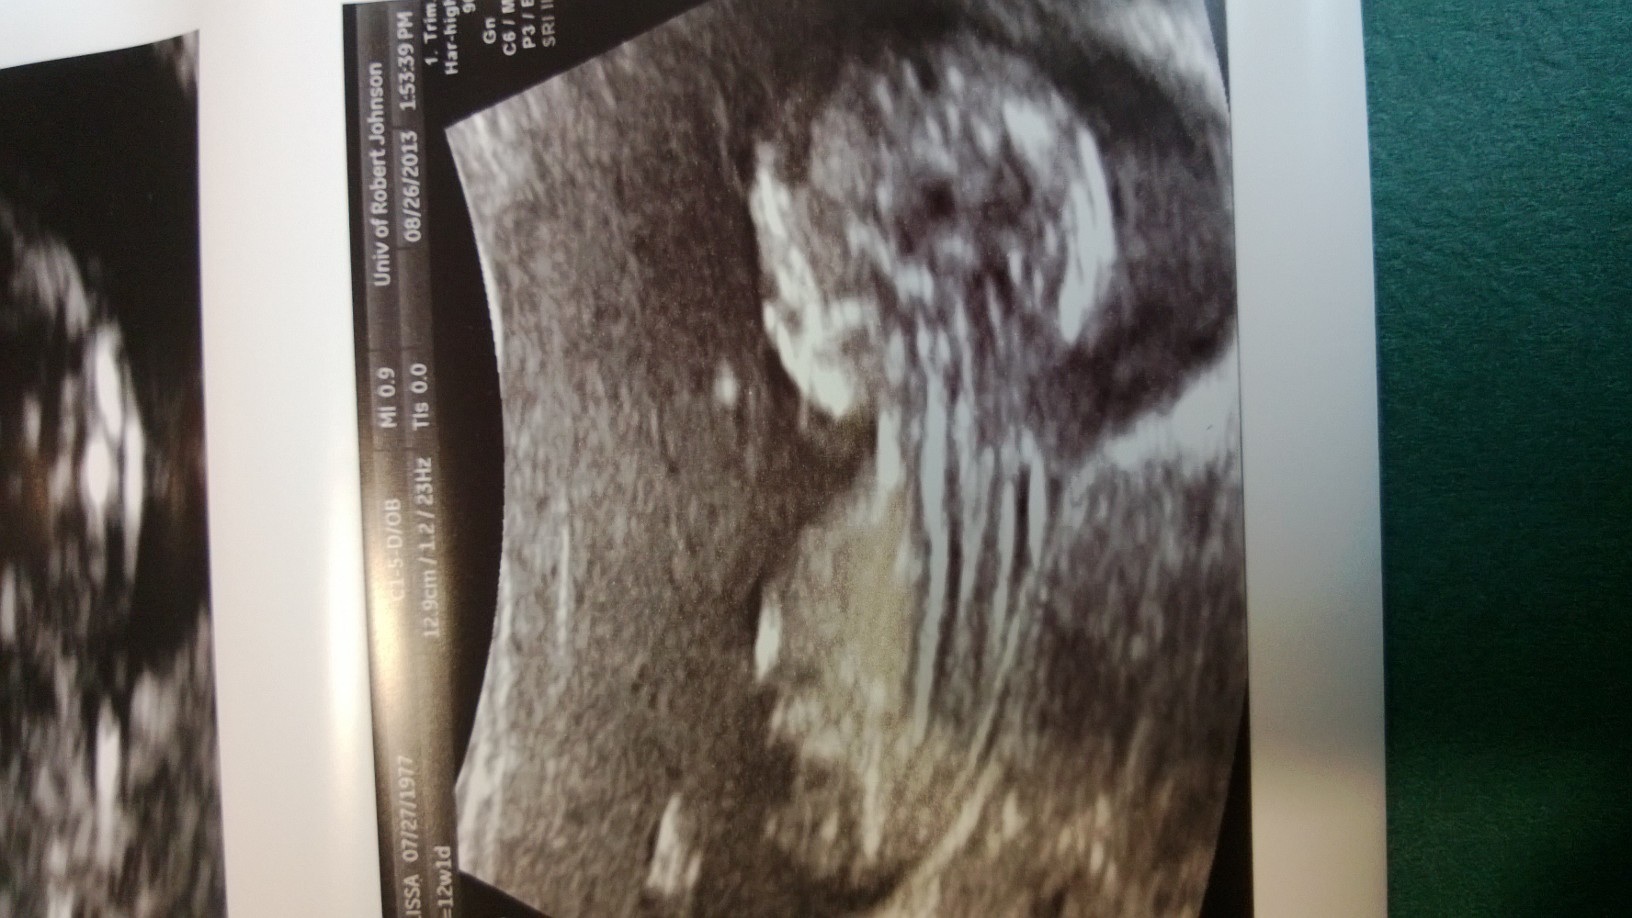

Had my NT ultrasound today and Harmony blood test. Now the 2 week wait for results. Keeping hopes high and fingers crossed. In the meantime here is a pic of my LO...

Oops hit the post button too soon LOL

image.jpg

What a great u/s pic!